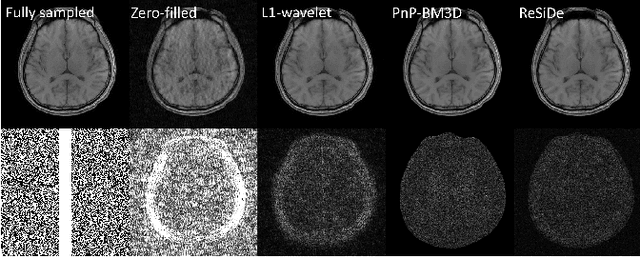

Abstract:Plug-and-play (PnP) methods that employ application-specific denoisers have been proposed to solve inverse problems, including MRI reconstruction. However, training application-specific denoisers is not feasible for many applications due to the lack of training data. In this work, we propose a PnP-inspired recovery method that does not require data beyond the single, incomplete set of measurements. The proposed method, called recovery with a self-calibrated denoiser (ReSiDe), trains the denoiser from the patches of the image being recovered. The denoiser training and a call to the denoising subroutine are performed in each iteration of a PnP algorithm, leading to a progressive refinement of the reconstructed image. For validation, we compare ReSiDe with a compressed sensing-based method and a PnP method with BM3D denoising using single-coil MRI brain data.